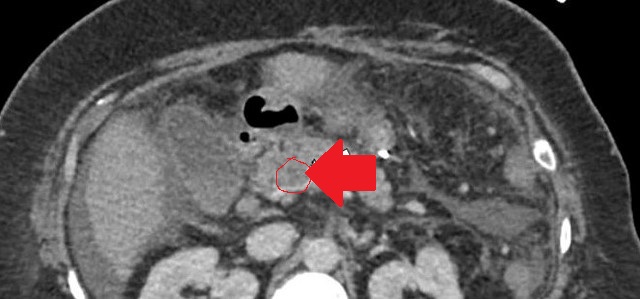

Mesenteric root infiltration — Absolute contraindication for cytoreductive surgery (Courtesy Dr. V. Penopoulos)